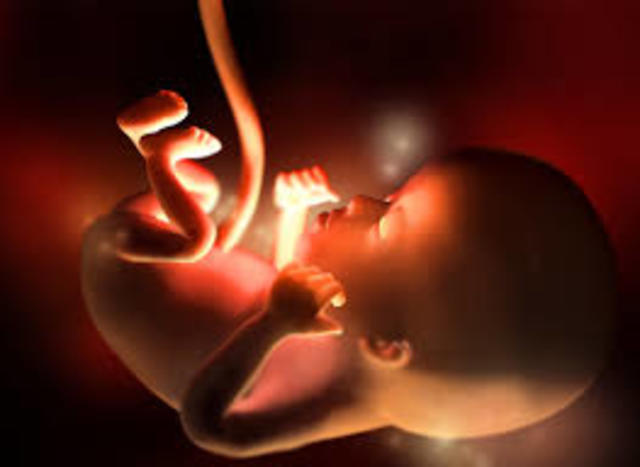

• Semana 26 a 29 de embarazo

Semana 26 a 29 de embarazo

Su sistema nervioso es capaz de controlar los movimientos respiratorios y la temperatura.S us movimientos on más activos, su estómago, intestino y riñones funcionan perfectamente. Todos sos órganos sensoriales están despiertos, los parpados y los ojos están completamente formados y comienzan a abrirse y cerrarse, comienza la freciencia cardiaca y a tener hipo.